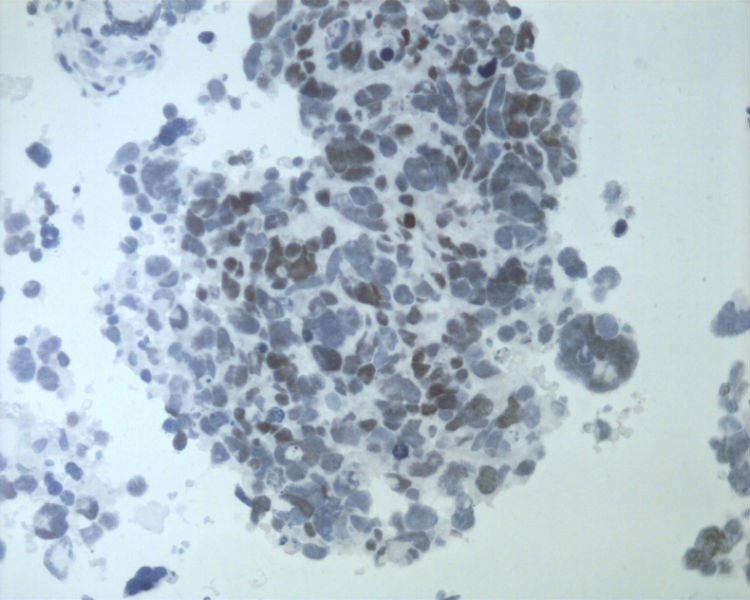

• 图1 TTF-1

名称:图1 CK

名称:图2 SYN

名称:图3 CD56

名称:图4 CGA

结合细胞腊块及免疫组化结果,诊断了淋巴结转移性的大细胞神经内分泌癌。

细胞块的细胞成分多且有成团趋势,加上IHC支持肺来源的大细胞神经内分泌癌转移至颈部淋巴结。